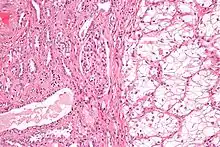

Anatomopathologie

Elle est basée essentiellement sur l'examen anatomopathologique de la pièce chirurgicale d'exérèse, la biopsie n'ayant que peu d'utilité. La classification anatomo-pathologique des tumeurs du rein est la classification UICC.

90 % des cancers du rein sont des carcinomes à cellules rénales, répartis en différents types histologiques[13] :

- Carcinome à cellules claires du rein (80 à 90 %)

- Carcinome papillaire subdivisé en Carcinome papillaire de type 1 et Carcinome papillaire de type 2[24] (10 à 15 %)

- Carcinome à cellules chromophobes (4 à 5 %)

- Carcinome des tubes collecteurs

- Carcinome inclassable